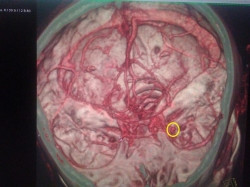

Бывают случаи, когда пациент жалуется на головную боль, частичную потерю или затуманенность зрения, онемение, боль в глазах. Невролог подозревает патологию сосудов головного мозга и направляет человека на МСКТ. Уже на исследовании выясняется, что причиной состояния была аневризма – образование на кровеносном сосуде, которое быстро растет и наполняется кровью. На снимках аневризма выделена кругом. Разрыв ее может привести к кровоизлиянию в головном мозге – это опасное для жизни состояние. При разрыве человек ощущает самую сильную боль, и нуждается в помощи врача.